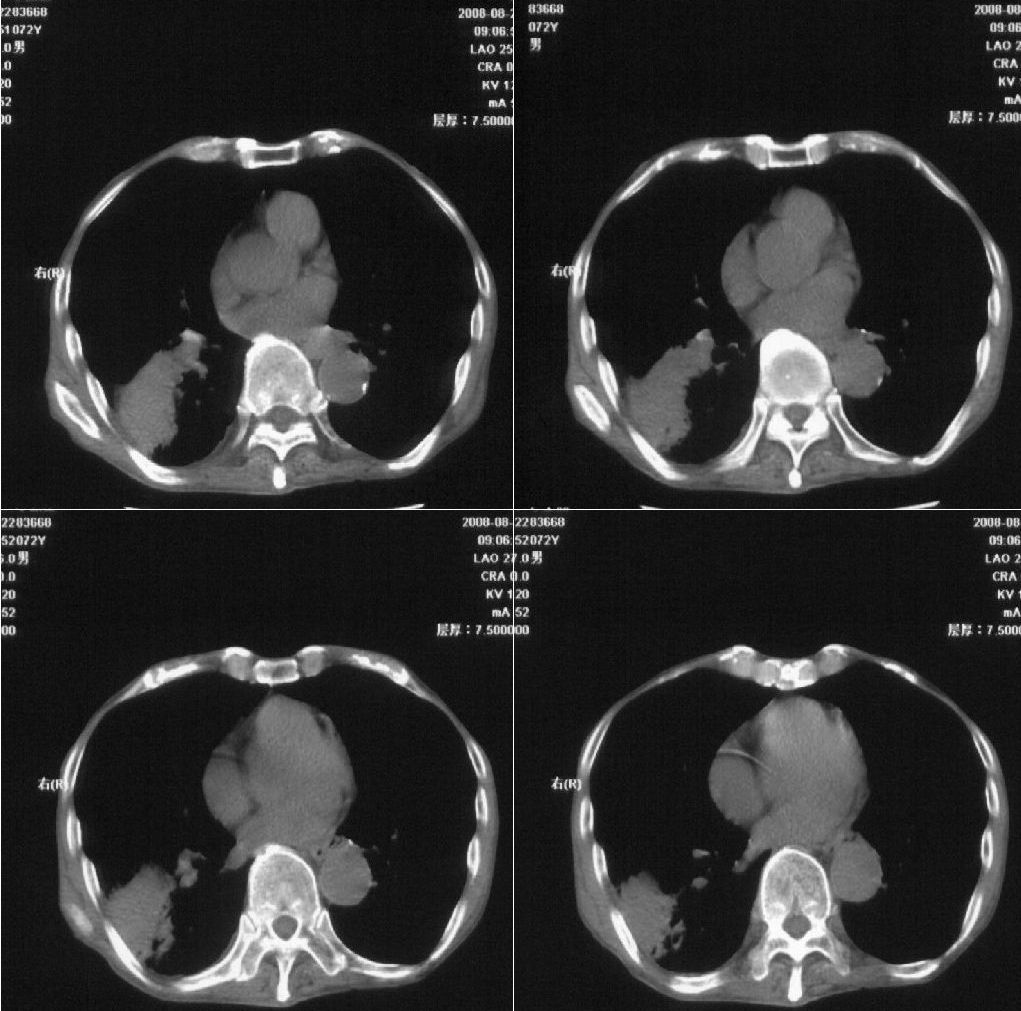

标题: CT15789:男性,72岁。食管癌术后14年。 [打印本页]

标题: CT15789:男性,72岁。食管癌术后14年。

痰培养:见葡萄球菌,霉菌少量生长。(此片系外院所作,仅提供了增强后的ct值为100hu,中心的坏死部分无强化,患者现在身体状况欠佳,为恶液质状态)

注意排外食管支气管瘘引起的肺部感染

符合机遇性感染,真菌可能性大。

该患者通过抗炎治疗明显好转:当时患者消瘦,实是因为患者进食量不多。患者有食道癌,因发生原发肺癌的机率并不高,当时的ct片除了增强感觉有强化外(其实这信息也并不确定,因为是外院ct),其实并没有发现支气管腔改变等直接征象。经过治疗,患者现在一般情况良好。以下是9月22日的复查片,发现病灶吸收明显。纵隔窗就不上传了。